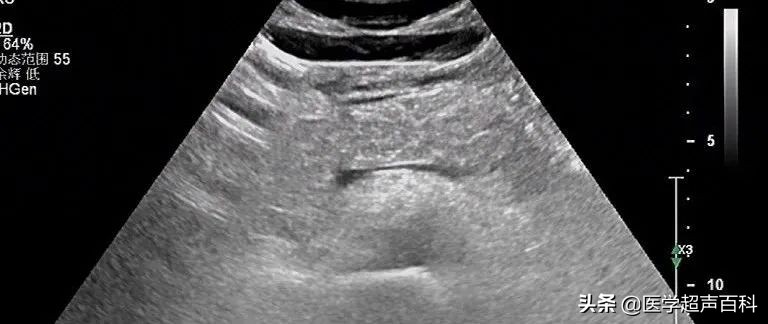

水肿型胰腺炎:胰腺稍大, 边缘规整,胰头、体部回声减低,分布前均质

急性胰腺炎声像图表现

(1)胰腺弥漫性或局限性增大,可失去正常形态,轮廓不清。

(2)内回声减低,呈弥漫分布的弱点状,中间有强弱不均、形态不整、边界不清的片状回声。严重水肿时呈透声暗区,似囊肿声像图。